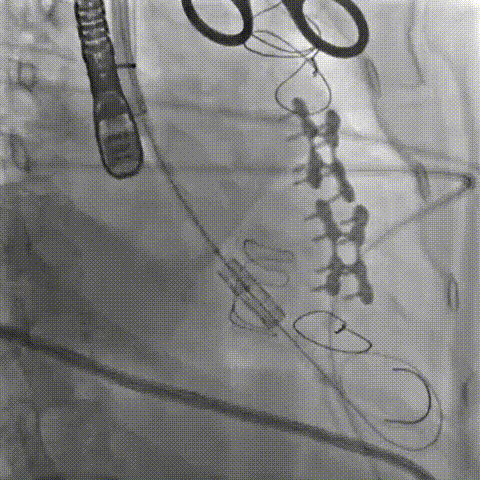

三尖瓣病例:

患者女性,62岁,既往三尖瓣位植入29# SAV猪瓣,超声提示三尖瓣人工瓣膜衰败,压差升高伴重度关闭不全。患者合并房颤伴长间歇、巨大右房、右心功能差,经独立专家委员会评判该患者属于外科手术高风险。术前经详尽影像学测量及多学科讨论,反复模拟分别经股静脉及经颈静脉入路输送瓣中瓣至三尖瓣的角度后,发现经右侧颈静脉入路瓣膜输送角度更理想。

手术顺利,经右颈静脉入路成功植入27号Renato球扩式瓣中瓣。瓣膜植入位置理想,无瓣周漏及中央返流。经查阅现有资料,经颈静脉路径成功完成三尖瓣“瓣中瓣”治疗在国内尚属首例。

▲球扩三尖瓣 ▲右室造影